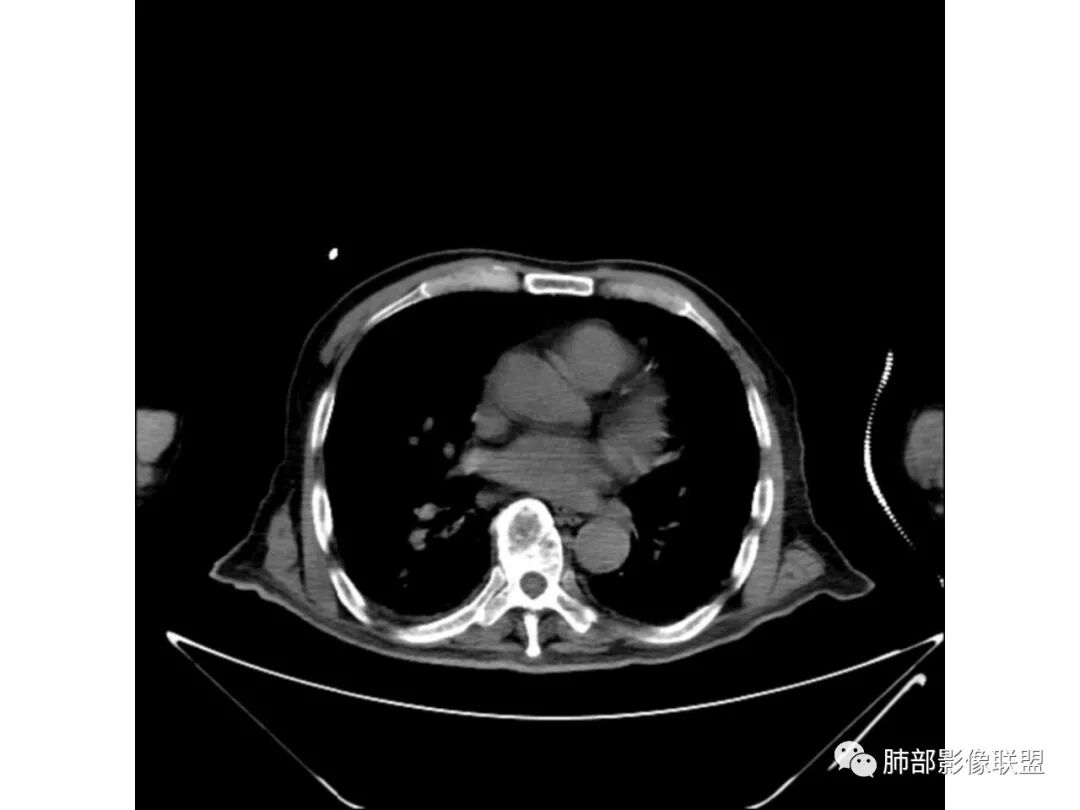

老年男性,既往糖尿病10年,右上肺不均匀实变+两肺实质及间质病变;本例良性感染性病变支持点:糖尿病史+双肺多发的实变,右上肺实变内可见支气管气像;恶性支持点:实变内的支气管似乎呈“枯树枝”样改变,纵隔有超过1.5cm的肿大淋巴结。

个人倾向良性感染性病变>恶性;考虑双肺混合性感染,右肺上叶实变拟结核可能性大,重点鉴别是弥漫浸润性肺腺癌。建议纤支镜检查。

葛良卫(随遇而安):

老年男性,糖尿病病史,咳嗽咳痰10余天入院。右上肺实变,见支气管充气征,部分支气管扩张,虫蚀样空洞,无壁空洞内壁光滑,实变病灶内见粘液成分,右上肺体积稍缩小,结核和肺炎性肺癌的鉴别,结核可能大,合并间质性肺病。

3、增强扫描很重要,增强后,结核的坏死很彻底,很少异常强化,(鳞癌也类同)。而粘液腺癌血管常显影,有时是毛糙的,整体密度偏低,哟其实纵膈窗。